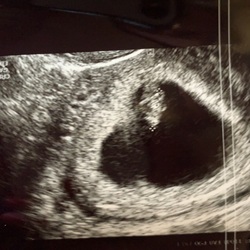

🙋♀️ hier ook en ben iets meer dan 6 weken ver... ik ben heel vaak geconstipeerd en vertering loopt echt traag.. met een opgeblazen gevoel en buikpijn tot gevolg